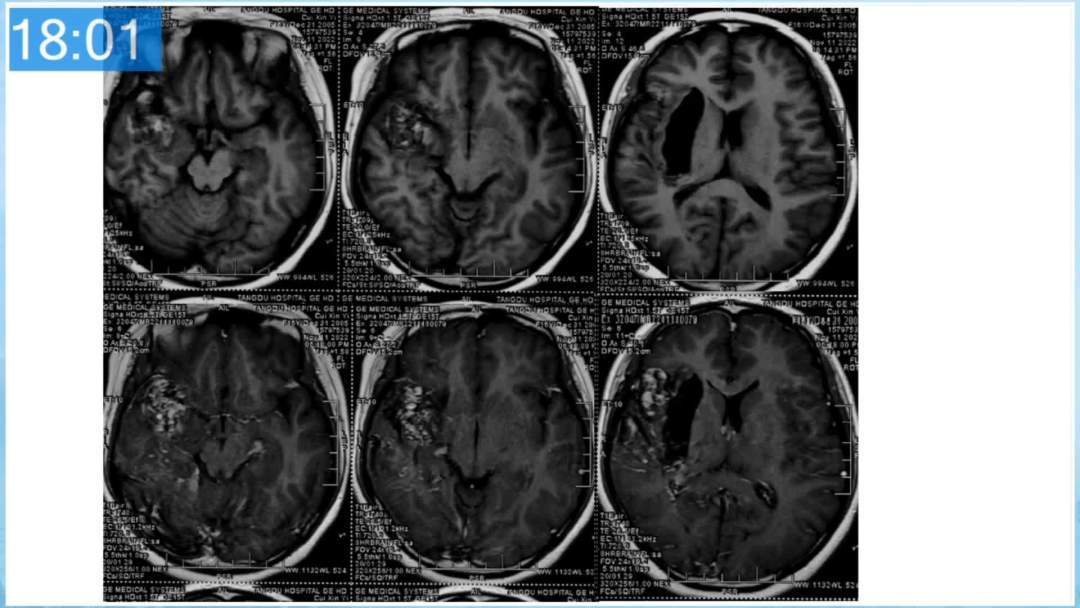

本期为大家特别分享:空军军医大学唐都医院邓剑平教授的精彩会议内容《颅内动静脉畸形的复合手术治疗》,欢迎大家阅读和分享!